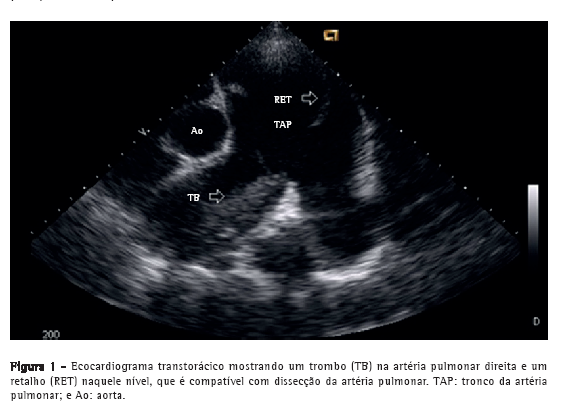

Paciente do sexo masculino, 50 anos, diagnosticado há quatro anos com hipertensão pulmonar relacionada à esquistossomose mansoni, admitido na emergência do Hospital das Clínicas da Faculdade de Medicina da Universidade Federal de Minas Gerais, localizado em Belo Horizonte, Brasil. Apresentava dor torácica retroesternal de início recente com agravamento progressivo e falta de ar (hipertensão pulmonar classe funcional III, de acordo com a Organização Mundial de Saúde). Havia sido diagnosticado com leucemia mieloide crônica há sete meses e estava em quimioterapia desde então. No momento da internação, o ecocardiograma transtorácico mostrava um grande trombo central não obstrutivo na artéria pulmonar principal direita. O átrio direito estava dilatado, e havia regurgitação tricúspide leve, com pressão sistólica em artéria pulmonar estimada em 63 mmHg. Foi diagnosticado como portador de trombose in situ como complicação de hipertensão pulmonar de longa duração. Após a possibilidade de síndrome coronária aguda ter sido excluída, recebeu alta em uso de varfarina. Foi reinternado dois meses depois em razão de dor torácica refratária com agravamento progressivo. Na época, apresentava SpO2 de 96%, e uma terceira bulha era audível no espaço paraesternal esquerdo inferior, acompanhada por murmúrio de regurgitação tricúspide. Os pulmões estavam limpos, e os pulsos arteriais periféricos estavam simétricos. Os exames laboratoriais estavam normais, incluindo os níveis séricos de creatinoquinase, creatinoquinase isoenzima MB e troponina. O eletrocardiograma de repouso evidenciava isquemia miocárdica aguda nas derivações anteriores. O ecocardiograma Doppler transtorácico revelava pressão sistólica da artéria pulmonar de 62 mmHg, um trombo na artéria pulmonar direita, como no exame anterior, e a presença de um retalho naquele nível que era compatível com dissecção da artéria pulmonar (Figura 1). O diagnóstico foi subsequentemente confirmado por angiografia pulmonar por TC (APTC; Figura 2). O paciente foi transferido para outro centro de tratamento cardiovascular, onde foram realizadas tentativas de correção do defeito por meio de um procedimento endovascular (através da veia femoral). No período perioperatório, o paciente apresentou choque cardiogênico refratário. Todos os esforços para reanimar o paciente foram infrutíferos, e ele faleceu na sala de cirurgia.